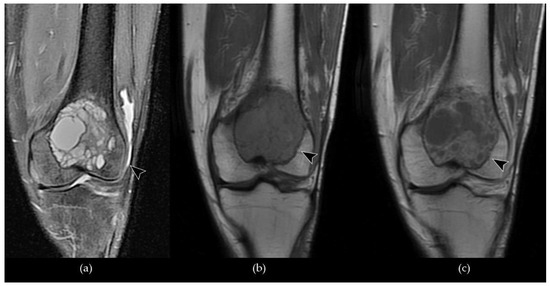

- Pereira, H.M.; Marchiori, E.; Severo, A. Magnetic resonance imaging aspects of giant-cell tumours of bone. J. Med. Imaging Radiat. Oncol. 2014, 58, 674–678. [Google Scholar] [CrossRef]

- Aoki, J.; Tanikawa, H.; Ishii, K.; Seo, G.S.; Karakida, O.; Sone, S.; Ichikawa, T.; Kachi, K. MR findings indicative of hemosiderin in giant-cell tumor of bone: Frequency, cause, and diagnostic significance. AJR Am. J. Roentgenol. 1996, 166, 145–148. [Google Scholar] [CrossRef]

- Nishibori, H.; Kato, H.; Kawaguchi, M.; Nagano, A.; Matsuo, M. T2*-weighted MR imaging findings of giant cell tumors of bone: Radiological–pathological correlation. Jpn. J. Radiol. 2019, 37, 473–480. [Google Scholar] [CrossRef]

- He, Y.; Wang, J.; Zhang, J.; Yuan, F.; Ding, X. A prospective study on predicting local recurrence of giant cell tumour of bone by evaluating preoperative imaging features of the tumour around the knee joint. Radiol. Med. 2017, 122, 546–555. [Google Scholar] [CrossRef]

- He, Y.; Wang, J.; Zhang, J.; Du, L.; Lu, Y.; Xu, J.; Yuan, F.; Tan, Y.; Ding, X. Magnetic resonance feature of “paintbrush borders” sign as a novel way to predict recurrence of giant cell tumor of bone after curettage: A pilot study. J. Int. Med. Res. 2018, 46, 710–722. [Google Scholar] [CrossRef]

- He, Y.; Wang, J.; Rui, W.; Lin, J.; Yuan, F.; Du, L.; Zhang, J.; Ding, X. Retrospective investigation of “paint brush borders” sign in association with local recurrence of giant cell tumor of bone after intralesional curettage. J. Bone Oncol. 2018, 10, 41–48. [Google Scholar] [CrossRef]